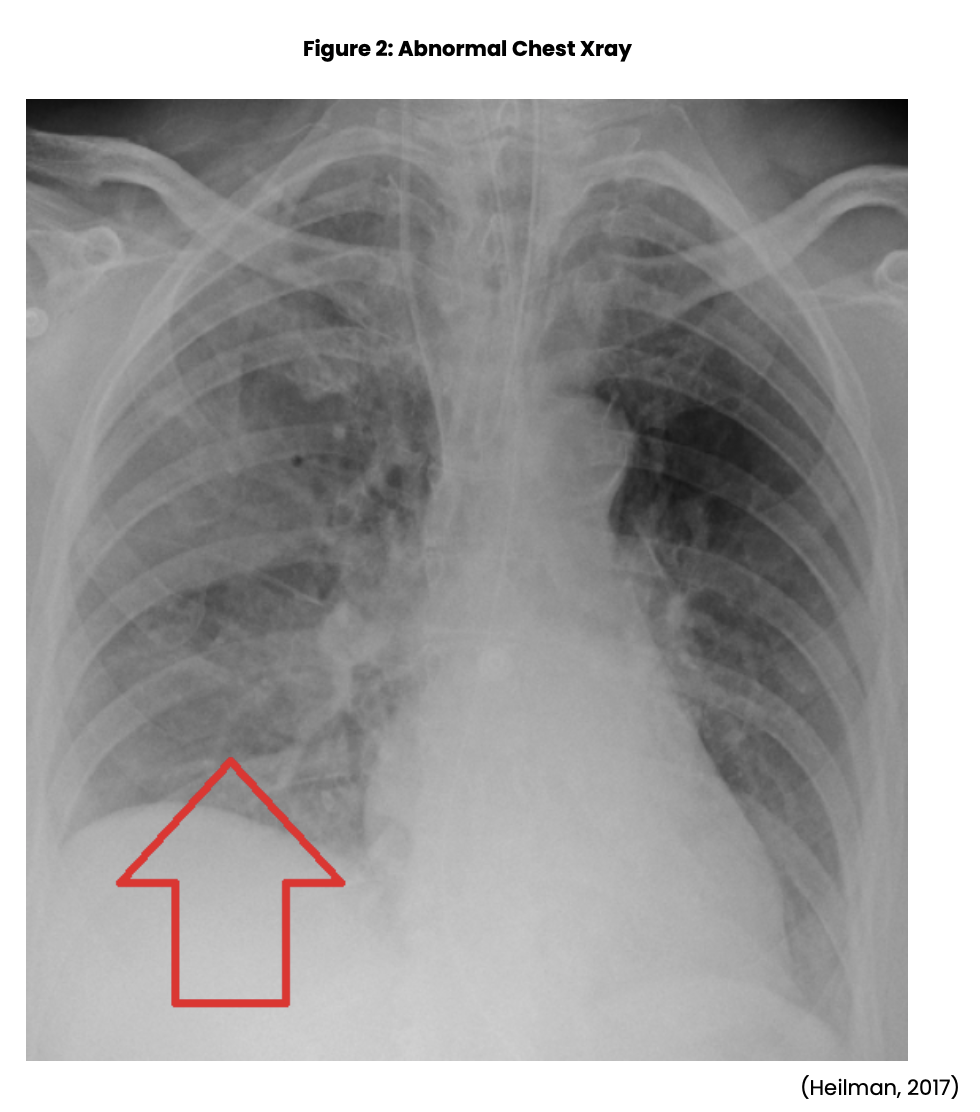

Postoperative Pulmonary Complications Clinical View Postoperative Complications Nursing Postoperative care begins at the end of the procedure and continues in the recovery room and throughout the hospitalization and. They are often experienced in a specialised area of surgery that requires specific care. Postoperative complications are often due to the interplay of multiple factors. Elderly patients continue to be at increased risk for postoperative complications. Awareness of these risk. Postoperative Complications Nursing.